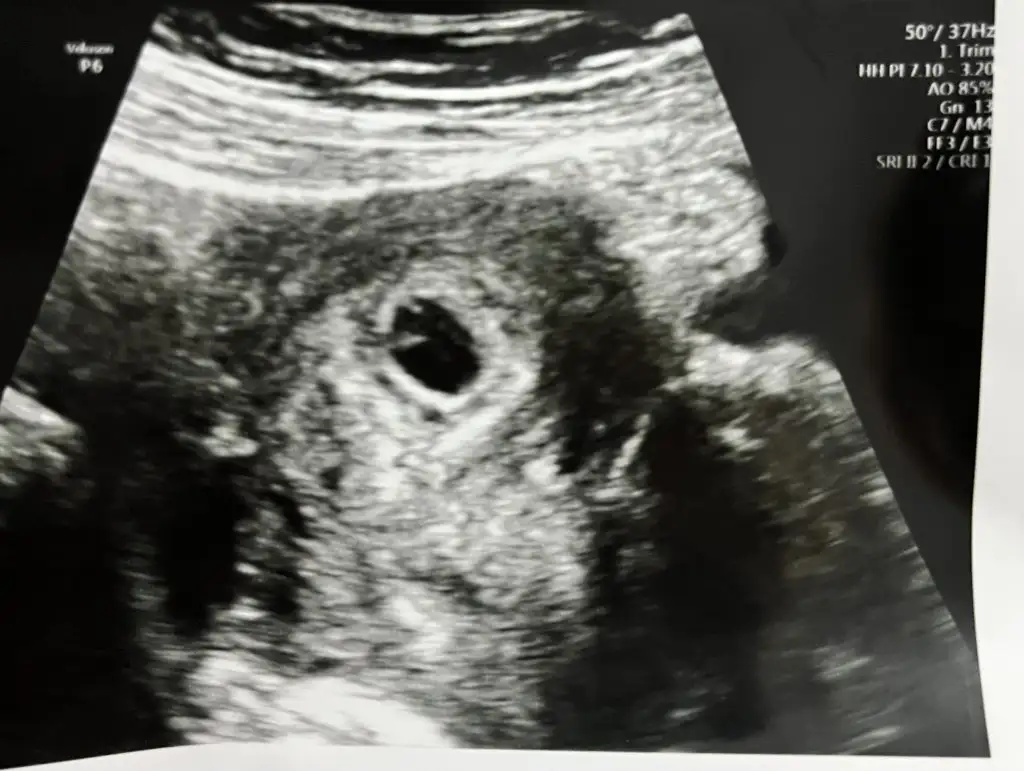

Kızlar 5.haftada keseyi görenlere bi sorum var. İçinde yolk sac nasıldı kesenizin içinde baya belli miydi nokta gibi miydi

Benim kesede yolk oluşmaya başlamış dedi bugün doktor. Aşağıya resmi bırakıyorum. Sanırım o içe doğru çıkıntılar oluşturacak